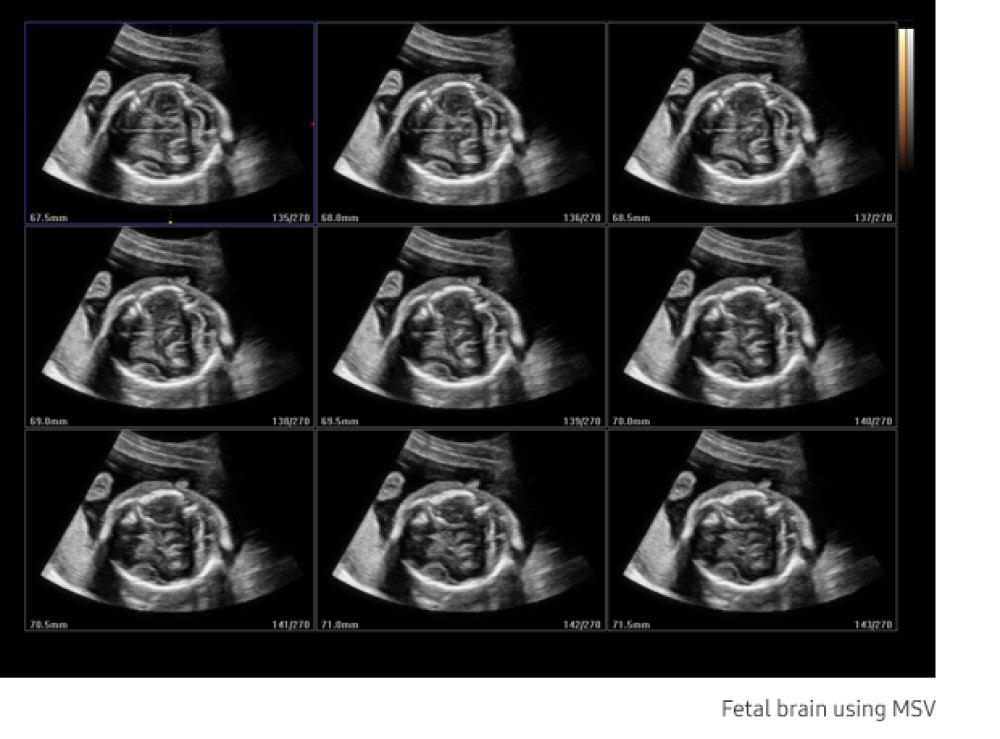

MultiVision™: Ultrasəs şüasını elektron olaraq idarə edir, çoxlu skan xəttlərini yönəldir və birləşdirir, beləliklə təsvir keyfiyyətini artırır. Məkan və kontrast çözünürlüğünü yüksəldir və artefaktları əvvəlkindən daha çox azaldır.

Samsung HS40 çoxşaxəli, orta səviyyəli ultrasəs sistemidir və obstetrika, ginekologiya, muskuloskeletal (MSK), abdominal, pediatrik, kiçik orqanlar, urologiya və vaskulyar görüntüləmə daxil olmaqla geniş klinik tətbiqlər üçün yüksək keyfiyyətli təsvir təmin edir. O, diaqnostik etibarlılığı və iş prosesinin səmərəliliyini artırmaq üçün qabaqcıl təsvir texnologiyalarını istifadəçi dostu xüsusiyyətlərlə birləşdirir.